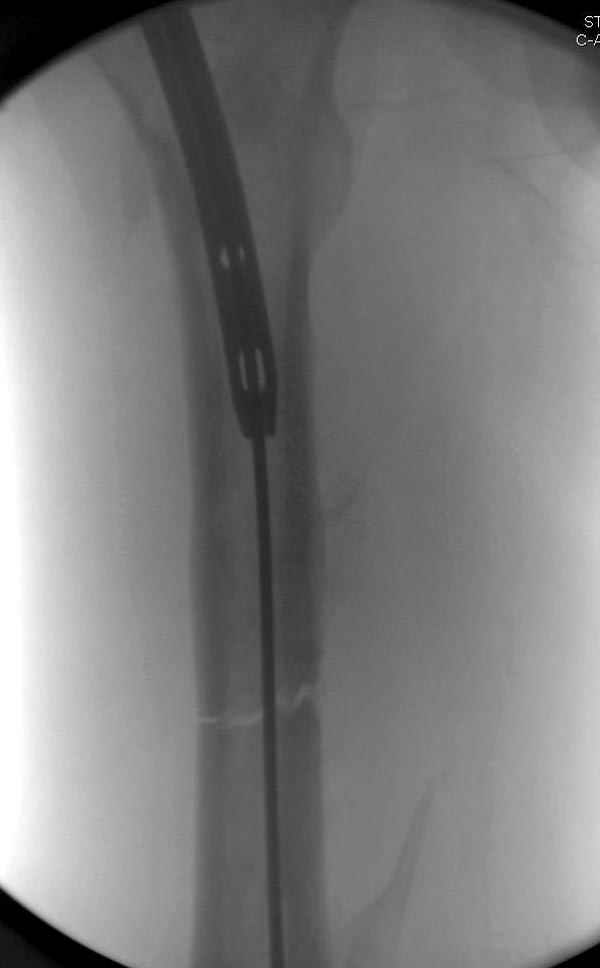

На следующий день произвели интрамедуллярный остеосинтез: этапы во время операции (рис №8, №9)

и последующих снимках (рис №10, 11, 12, 13) перелом сростается и передвигается с полной нагрузкой.